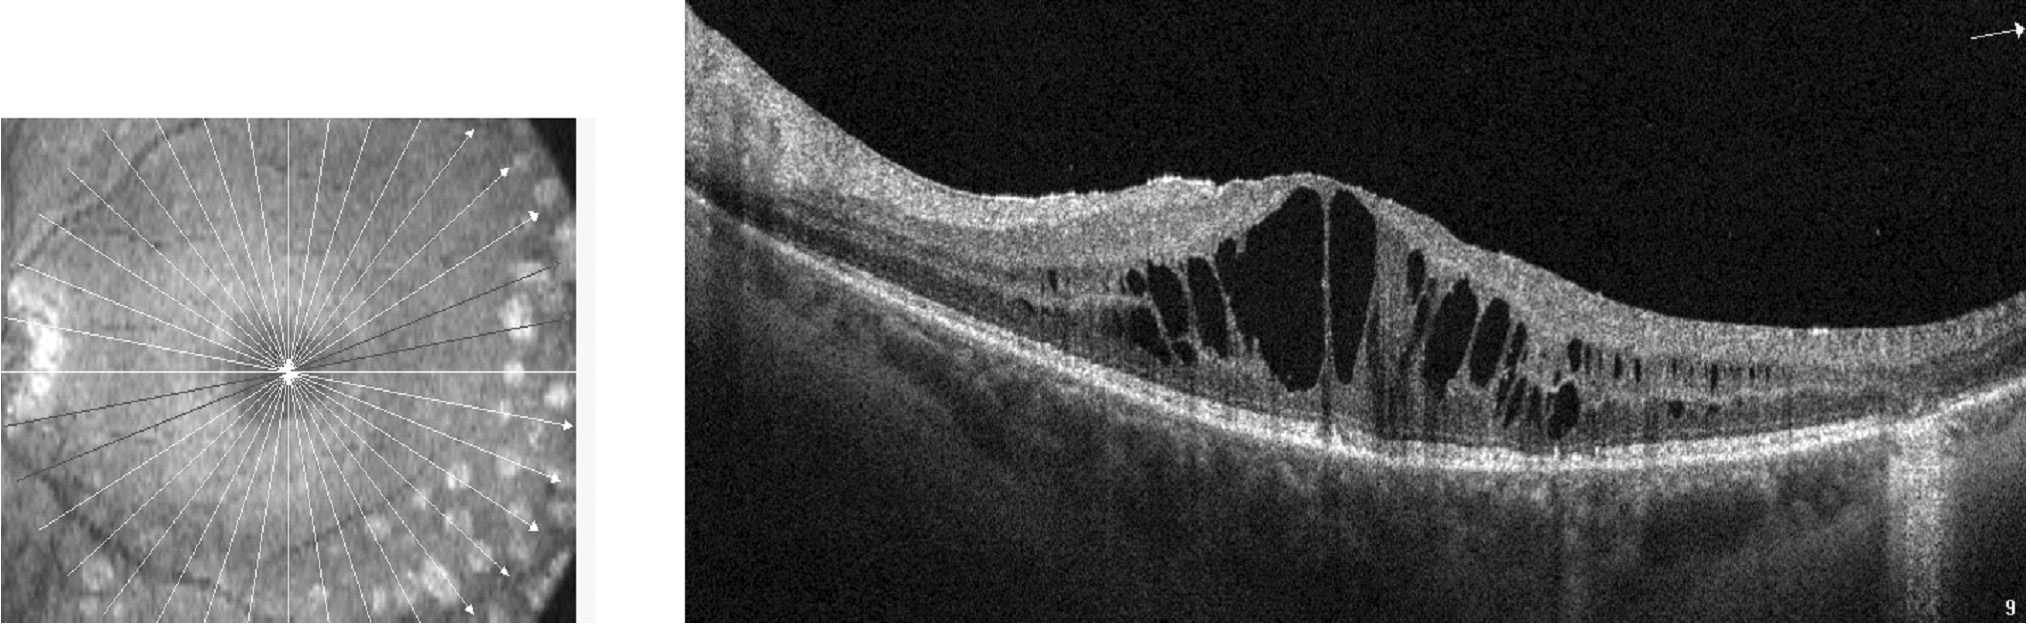

На рисунках 1 и 2 приведена типичная картина состояния сетчатки при ПДР без ДМО и при наличии ДМО по данным оптической когерентной томографии.

Рисунок 1. Сетчатка при пролиферативной диабетической ретинопатии без признаков отека. нейроэпителия.

Рисунок 2. Кистовидный макулярный отек.